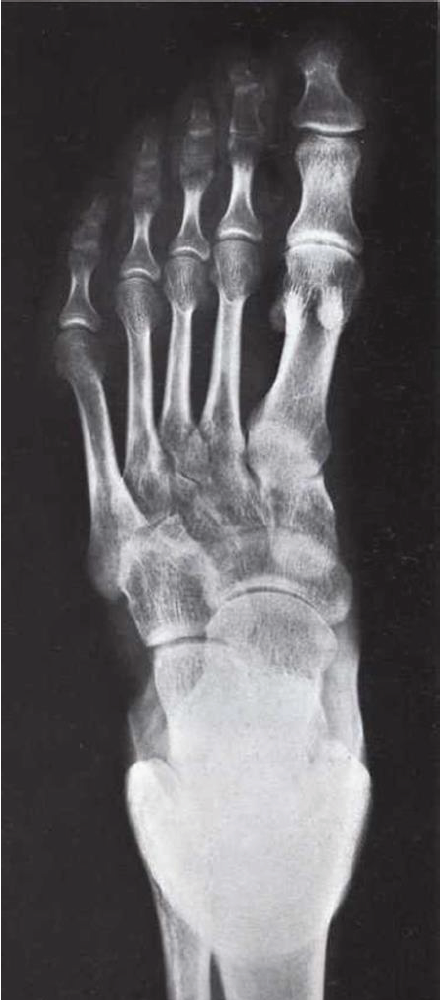

What is this view of the foot? what views are missing?

Oblique (medial)

MISSING:

Dorsal Plantar

Lateral